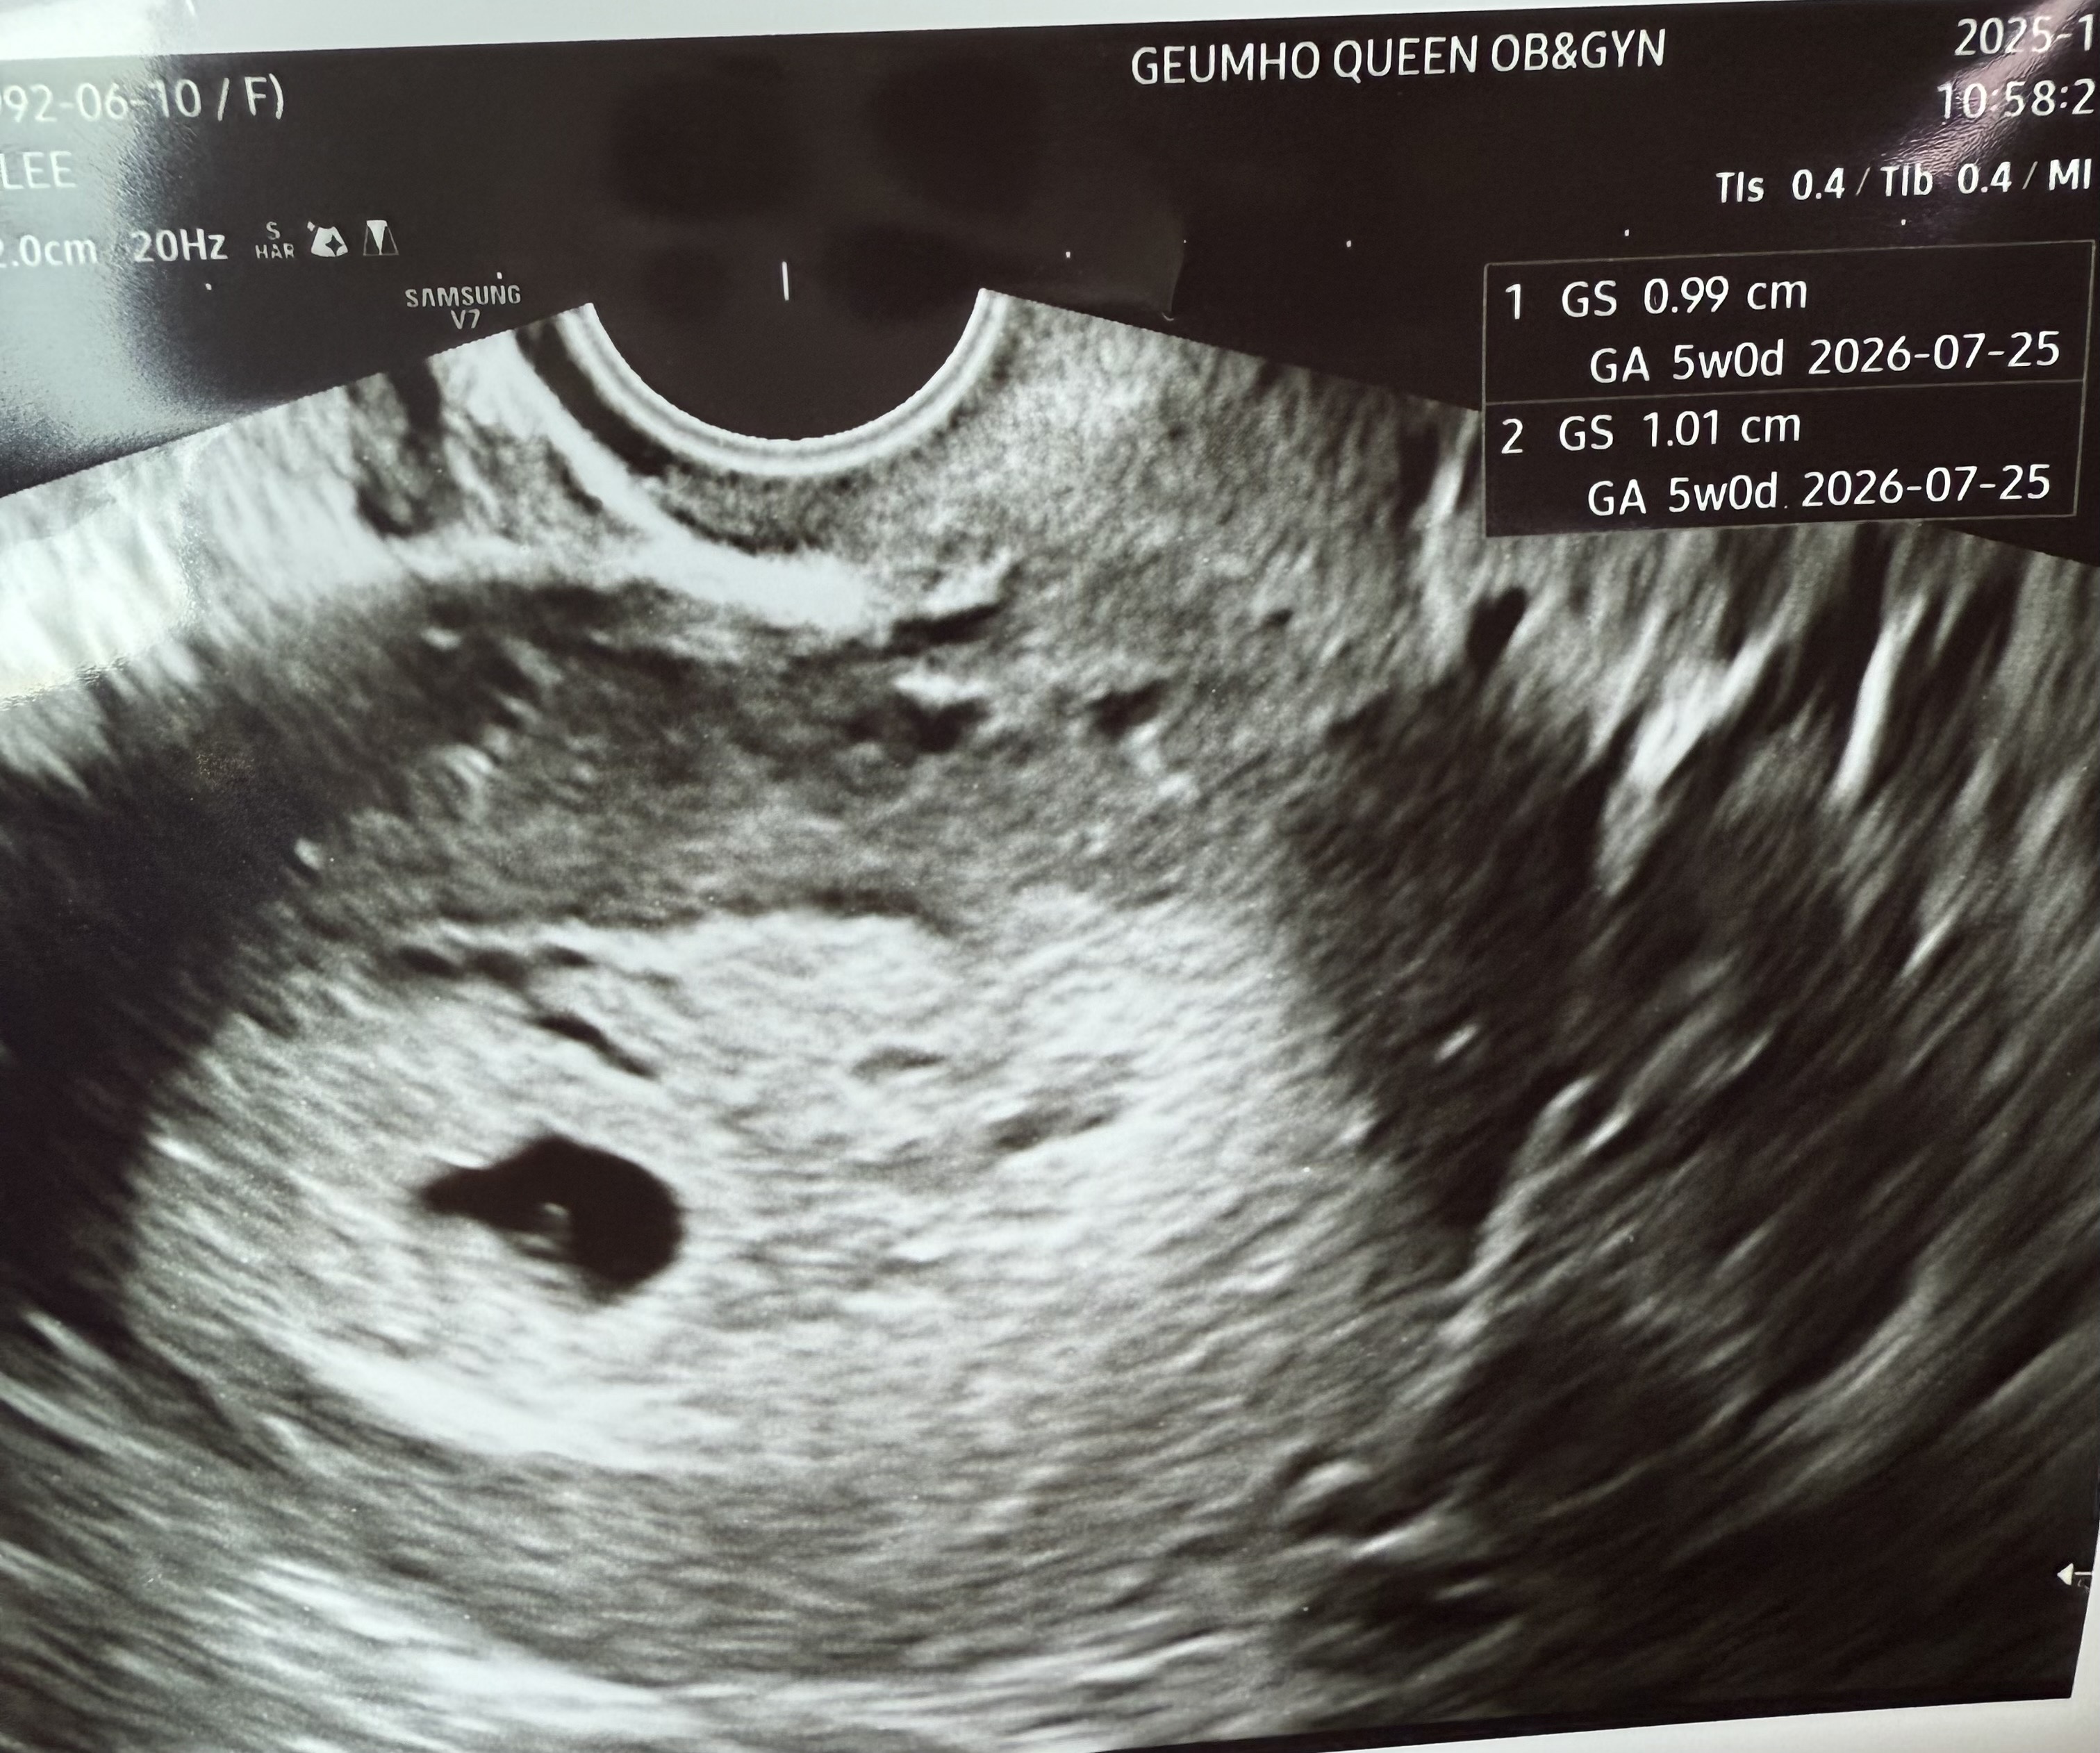

5주 0일에 딱 아기집+난황 보고 왔어요! 2주 뒤에 심장소리 듣게 남편이랑 오라고하셨는데 하루하루 시간이 안가서 미치겠네요ㅠㅠㅋㅋㅋㅋ 6주 0일에 서브병원이라도 가서 배아라도 보고싶은데.. 안보일수도 있을까요? 그냥 꾹 참는게 좋겠죠..? 😂😂